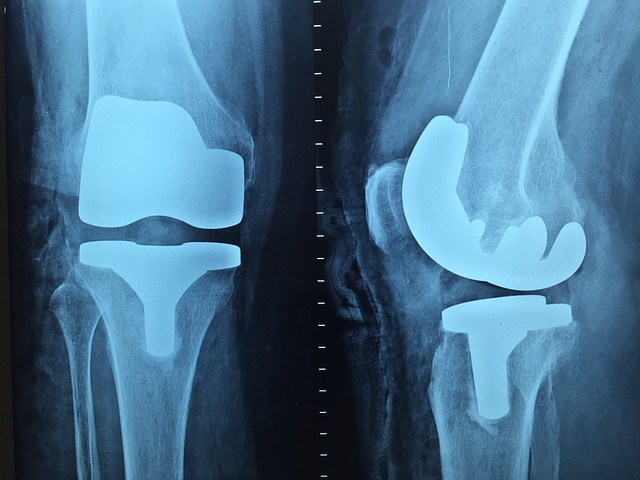

膝部分のレントゲン写真

Andersonvr

靭帯断裂は、身体の外からの強い力に靭帯が耐えきれなくなり、切れたり伸びきったりする状態をいいます。交通事故であれば、加害者の車や障害物などにぶつかった際の衝撃などが、要因になります。交通事故で特に多いのは、膝の靭帯断裂です。

1つ目のポイントは、画像による靭帯断裂の確認の検査を、受診することです。ただし、組織体である靭帯断裂は、レントゲン検査による確認ができません。

そのため、患部のMRI検査を受ける必要があります。MRI画像は、後遺障害認定を判断する際に、有効的な資料になります。

3つ目のポイントは、検査で後遺症であることの裏付けを取るという点です。MRI検査以外で、靭帯断裂を確認する方法として、ストレスレントゲン撮影という検査があります。

この検査では、靭帯断裂した箇所を直接撮影するのではなく、医師が手や器具を使い、脛骨を前後左右に動かします。こうして膝関節がずれた状態を作り、レントゲン写真を撮影するというものです。

そして、膝に不自然なぐらつきがないかを測定し、異常が認められれば、所見を診断書に記載します。このずれは、後遺症の一つである動揺関節の疑いがあることの、証明となります。